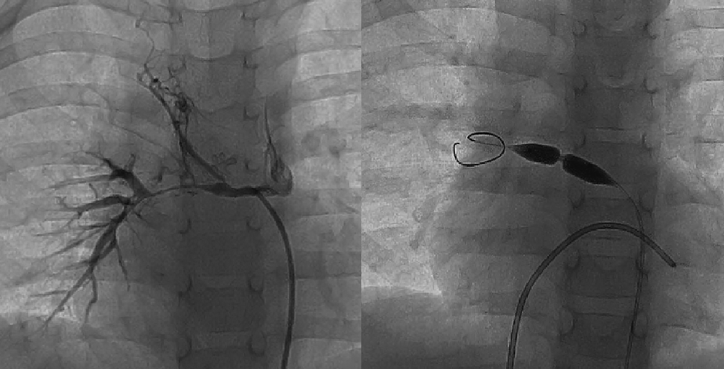

経皮的バルーン血管形成術は,血管狭窄病変を内腔より拡張し,内膜から中膜にかけて一時的な亀裂・解離を生じさせることで,より大きな血管内径へのリモデリングを促し血行再建することを目的とする治療である(Fig. 11).日本先天性心疾患カテーテル治療学会(JCIC)データベースによると,本邦で実施される先天性心疾患カテーテル治療年間約4,500例のうち,経皮的バルーン血管形成術は約1,600例(36%)を占める2).新生児から成人まで幅広い年齢・体格を対象とするとともに,難易度の高いカテーテル治療手技へ向けた基本となるため,先天性心疾患カテーテル治療医を目指す医師にとって習熟すべき手技である.本稿では最も一般的に行われる肺動脈狭窄症に焦点を当て解説する.

Fig. 1 Upper and lower panels show angiographic and intravascular ultrasound findings before and after transcatheter balloon angioplasty, respectively. Intravascular ultrasound shows that a laceration of the intima follows a dissection between the intimal and medial layers, which promote vascular remodeling and achieve a larger diameter of the vessel. Schemes of the vascular remodeling show the pathophysiology of vascular remodeling (the right side).